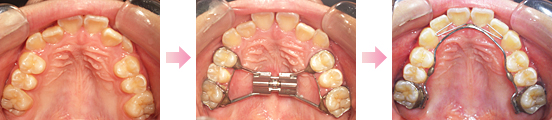

正常な咬み合わせができあがっていくための障害となる要素があった場合、それを取り除き自律的に永久歯列が完成するような口腔環境をつくる考えを基にしております。

可撤性の装置(取り外し可能)や部分的なワイヤー治療にて、比較的負担の少ない装置での治療となります。

治療期間は1年~3年くらい、または小学校6年~中学1年くらいまでが目安になります。

正常な永久歯列を完成することを目的としております。術後の経過観察を行い治療完了となり、その後再び矯正治療の可能性が少ないと言えます。

永久歯の抜歯が必要な症例などは本格矯正の考えの治療と言えます。